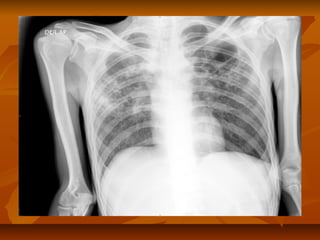

toma. Radiológicamente se observan infiltradostoma. Radiológicamente se observan infiltrados

pulmonares con retracción de lóbulos superiores,pulmonares con retracción de lóbulos superiores,

casquetes pleurales, cavidades, desviación traqueal,casquetes pleurales, cavidades, desviación traqueal,

nódulos calcificados.nódulos calcificados.